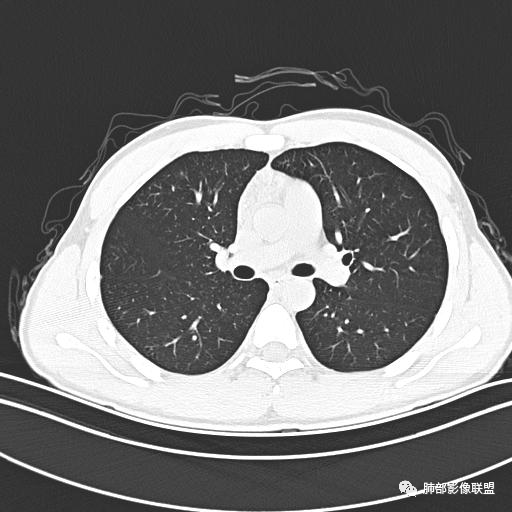

男,19岁

主  诉:发热、全身皮疹2天。

现病史:患者源于2天前受凉后出现发热,最高体温为38.5℃,且颜面部出现少量皮疹,无鼻塞、流涕、咳嗽、咳痰,未在意而未作特殊处理,次日全身皮疹逐渐增多至全身,伴轻度瘙痒,在当地卫生所给予抗病毒、抗感染治疗(具体用药不详)体温有所下降,但皮疹无明显消退,无腹痛、头痛,食欲无明显减退,为进一步诊治,遂于今日急来我院求治,患者目前精神尚可,体力正常,食欲正常,睡眠正常,体重无明显变化,大便正常,排尿正常。

小强:青年,发热,皮疹;双肺散在结节,周围磨玻璃,点晕征,疱疹病毒感染,鉴别荚膜组织胞浆菌,结核。 大雄:青年,急性起病,发热伴全身皮疹2天,抗病毒治疗体温有下降。双肺随机分布大小不等类圆结节,“点晕征”。考虑水痘-疱疹病毒(VZV)血播询问接触史,查体皮疹分布以及形态基本可诊断。 王开金江津中心医院呼吸科:青年男性,起病急,病程短,以发热,皮疹为首发症状,感染指标以单核细胞升高为主,胸部ct双肺多发结界,周围有晕,点晕表现,随机分布,同意於老师意见,水痘疱疹病毒血流感染累及肺。 王秀仙:双肺多发大小不等结节,周围有晕,边缘模糊,呈点晕征表现。青年,急性起病,发热伴全身皮疹2天,抗病毒治疗体温有下降。考虑疱疹病毒。鉴别荚膜组织胞浆菌。 傅昌瑜:19岁男性,发热、全身皮疹2天,单核细胞增高,双肺多发结节,结节边缘见边界不清磨玻璃影。点晕征+发热、全身皮疹+单核细胞增高——考虑水痘-带状疱疹病毒肺炎。 一切∮随缘:年轻男性,发热,皮疹两天,实验室,CRP,PCT增高,影像:双肺多发散在磨玻璃结节,边界欠清,大小不等,呈点晕征改变,以血管束周围分布为主,局部血管束略增粗,其它无明显改变,考虑:1:病毒性肺炎(水痘疱疹病毒?不知道皮肤有无改变)2:真菌(组织胞浆菌,血管侵袭性肺曲霉)3:GPA4:寄生虫(实验室没有看到嗜酸细胞增高) 赵山河:双肺散在结节,周围有晕,边缘模糊,呈点晕征表现。青年,急性起病,发热伴全身皮疹2天,抗病毒治疗体温有下降。考虑水痘—疱疹病毒感染。洪桥爱:青年男性,发热、皮疹2天,伴瘙痒,皮疹于面部首发,之后进展至全身,虽然没有对皮疹进行描述,但是从出疹时间及皮疹进展情况,伴瘙痒,应该就是个水痘患者;CT提示双肺随机分布结节影,部分结节伴有边界不清晕征,考虑水痘血播肺。 刘强:年轻男性,急性起病,皮疹,发热,抗感染治疗体温下降,说明有效。影像表现为散在点晕征,感染类疾病谱(疱疹病毒,真菌,结核),结合年龄,皮肤皮疹,考虑水痘-疱疹病毒性肺炎。 小兜:男性,19岁,发热皮疹两天,颜面部至全身,CRP,降钙素及单核增高。CT示双肺散在小结节,周围伴磨玻璃影,点晕征,考虑为水痘-带状疱疹病毒(varicella-zoster virus,VZV)肺炎 必有路:青年,皮疹+发热+“点晕征”→水痘-疱疹病毒(VZV) 许慧良:青年男性患者,发热、皮疹2天,体温最高38.5℃,第3天皮疹扩展至全身,伴瘙痒,胸部CT:双肺多发随机分布的小结节,结节周边见边界模糊的晕征,考虑水痘病毒感染流心明智:男,19,急性起病,发热伴全身皮疹2天。出疹顺序头→全身,抗病毒有效。胸部CT:两肺多发大小不等类圆形实性小结节影,随机分布,结节周围环绕GGO,边界模糊,呈点晕征。出疹特点是关键,未提示。考虑:血播病毒性肺炎,水痘-疱疹病毒?麻疹?鉴别荚膜组织胞浆菌、TB、血管炎、寄生虫等。 浪迹天涯:病灶多为5-10mm大小结节,结节周围可见磨玻璃样的晕环,常多发,可分布于肺内任何区域,考虑水痘—带状疱疹病肺炎如果短时间内有新的一个区域浸润,更加能说明,